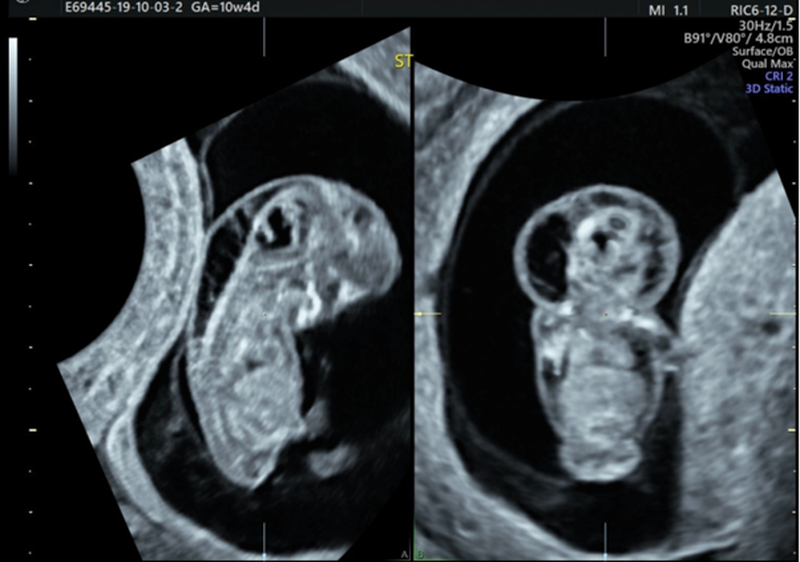

Nhiều chị em thắc mắc thai được 11 tuần đo độ mờ da gáy được chưa? Được biết, thời gian khuyến cáo để mẹ bầu thực hiện siêu âm độ mờ da gáy đó là từ tuần 11 đến tuần 14, thời điểm này lượng dịch tiết ra vửa đủ, dễ đo, cũng không nên thực hiện quá sớm sẽ có kết quả không chính xác và không còn ý nghĩa sàng lọc dị tật.

Độ mờ da gáy 1.2 là gì? Có nguy hiểm cho thai nhi không? 2 Siêu âm độ mờ da gáy đúng tuần của thai nhi sẽ có kết quả chính xác.